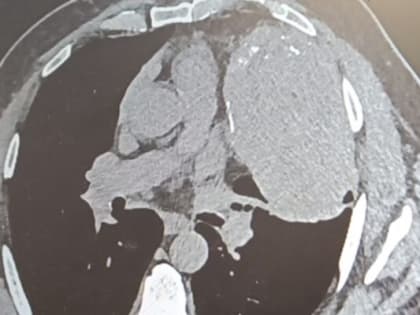

Снимок внутренних органов. Источник: Минздрав Оренбургской области В Оренбурге врачи удалили огромное новообразование в грудной клетке у жителя Орска, которое начало формироваться между сердцем,